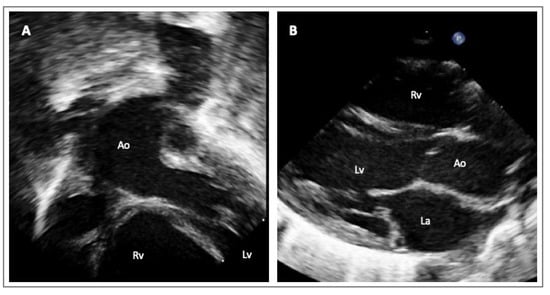

3. Genetics in HTADs

- Evangelista, A.; Sitges, M.; Jondeau, G.; Nijveldt, R.; Pepi, M.; Cuellar, H.; Pontone, G.; Bossone, E.; Groenink, M.; Dweck, M.R.; et al. Multimodality imaging in thoracic aortic diseases: A clinical consensus statement from the European Association of Cardiovascular Imaging and the European Society of Cardiology working group on aorta and peripheral vascular diseases. Eur. Heart J. Cardiovasc. Imaging 2023, 24, e65–e85. [Google Scholar] [CrossRef] [PubMed]

- Steinbrecher, K.L.; Marquis, K.M.; Braverman, A.C.; Ohman, J.W.; Bhalla, S.; Lin, C.Y.; Naeem, M.; Raptis, C.A. Imaging of Genetic Thoracic Aortopathy. Radiographics 2022, 42, 1283–1302. [Google Scholar] [CrossRef]